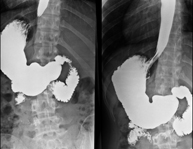

Tècnica que usa els raigs X a través de la qual s'obtenen imatges de la columna lumbar per al seu estudi. - TEGD (trànsit esòfag-gastro-duodenal)

Prova diagnòstica que consisteix en obtenir imatges radiològiques en moviment de l'esòfag, estómac i duodè mitjançant l'ús de raigs X (fluoroscòpia) i d'un contrast opac baritat que s'administra per via oral. - Trànsit intestinal

Prova diagnòstica que consisteix en obtenir imatges radiològiques en moviment de l'esòfag, estómac, duodè i intestí prim mitjançant l'ús de raigs X (fluoroscòpia) i d'un contrast opac baritat que s'administra per via oral. - Ènema opac doble contrast